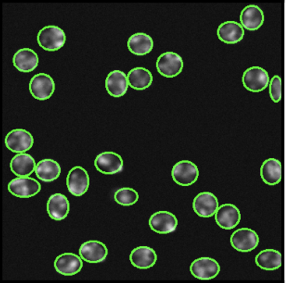

Cell detection in microscopy images is important to study how cells move and interact with their environment. Most recent deep learning-based methods for cell detection use convolutional neural networks (CNNs). However, inspired by the success in other computer vision applications, vision transformers (ViTs) are also used for this purpose. We propose a novel hybrid CNN-ViT model for cell detection in microscopy images to exploit the advantages of both types of deep learning models. We employ an efficient CNN, that was pre-trained on the ImageNet dataset, to extract image features and utilize transfer learning to reduce the amount of required training data. Extracted image features are further processed by a combination of convolutional and transformer layers, so that the convolutional layers can focus on local information and the transformer layers on global information. Our centroid-based cell detection method represents cells as ellipses and is end-to-end trainable. Furthermore, we show that our proposed model can outperform fully convolutional one-stage detectors on four different 2D microscopy datasets. Code is available at: https://github.com/roydenwa/cell-centroid-former